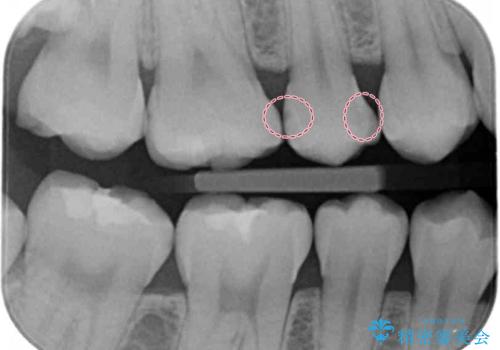

症状はないものの奥歯に黒ずんだ箇所があるため治療を進めていくことになりました。

外からも確認できる虫歯だけでなく、歯の奥の面の虫歯も残さず除去しました。